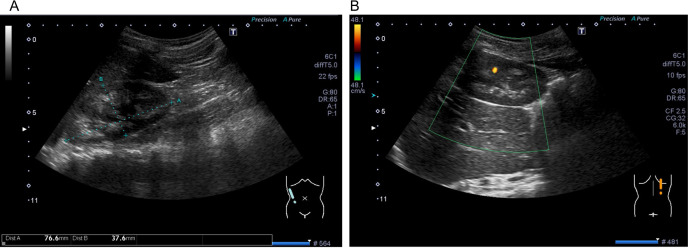

Idiopathic infantile hypercalcemia (IIH) is characterized by hypercalcemia, nephrocalcinosis, vomiting, dehydration, and failure to thrive. It is caused by the presence of biallelic loss-of-function variants in the CYP24A1 locus. Although hypercalcemia has been linked to the consumption of vitamin D-fortified milk, no reports have documented its role in triggering IIH in patients with CYP24A1 variants. Herein, we describe a case of IIH triggered by vitamin D-fortified milk consumption in a 9-mo-old male patient carrying a CYP24A1 variant. After BCG vaccination, the patient developed a facial rash, became anorexic, appeared to be in a bad mood, and began consuming vitamin D-fortified milk instead of baby food. Blood tests showed a marked hypercalcemia (18.5 mg/dL), high 1,25-(OH)2D (98.7 pg/dL) levels, and low parathyroid hormone (PTH) (< 4.0 pg/dL) and PTHrP (< 1.0 pg/dL) levels. The calcium levels were successfully normalized after treatment with saline loading, furosemide, pamidronate, and a low-calcium milk diet. After discharge, blood calcium levels remained normal with no recurrence of symptomatic hypercalcemia, but circulating PTH levels were persistently suppressed. Renal ultrasonography at 8 yr of age revealed high medullary echogenicity and diffuse echogenic foci in both kidneys. Trio-based whole-genome sequencing identified the following biallelic pathogenic variants c.[464G>A];[1324C>T], p.[Trp155Ter];[Gln442Ter], in the CYP24A1 (NM_000782.5) locus. Unexplained hypercalcemia in infants should raise suspicions of abnormal vitamin D metabolism and CYP24A1 locus genotypic analysis can be informative in this regard.